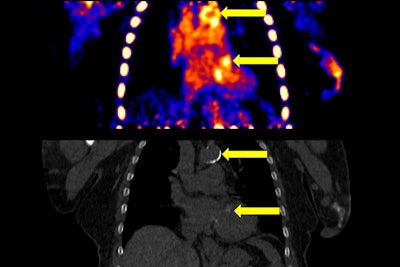

The image on top shows representative vascular calcifications (VCs) in both the aorta and heart in a F-18 NaF static PET image. The increased PET uptake in the VCs is concordant with increased signal and Hounsfield Unit density on the CT image below. BMC Nephrology